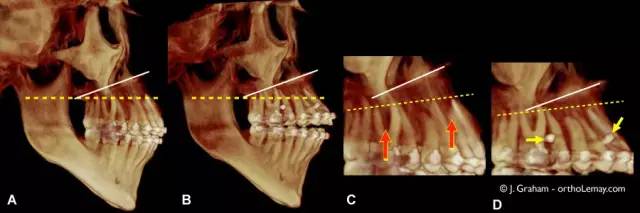

锥束CT(CBCT)。最初及最终治疗阶段。

3D扫描下,牙列抬高前后牙齿垂直方向位置的变化(CBCT)。